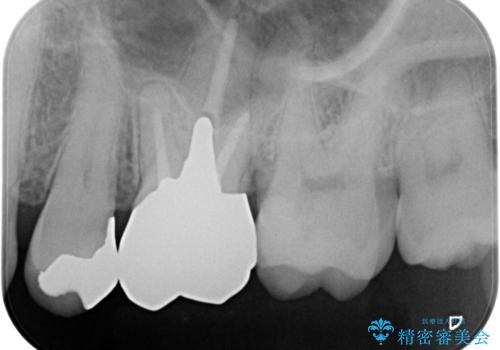

- 銀歯を白くしたいとの事で来院。まずは気になるところから治療していくという事になりました。

銀の被せ物を外し虫歯がないのを確認して、形を整えて白い被せ物の治療を行いました。

(再根管治療の提案をしたがご希望されませんでした。)